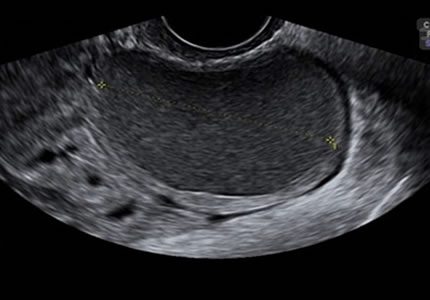

Comprehensive pelvic ultrasound evaluations for a wide range of non-pregnancy female health concerns, symptoms, or referrals.

Symptom-Based & Condition-Specific Scans

Device & Surgical Follow-Up